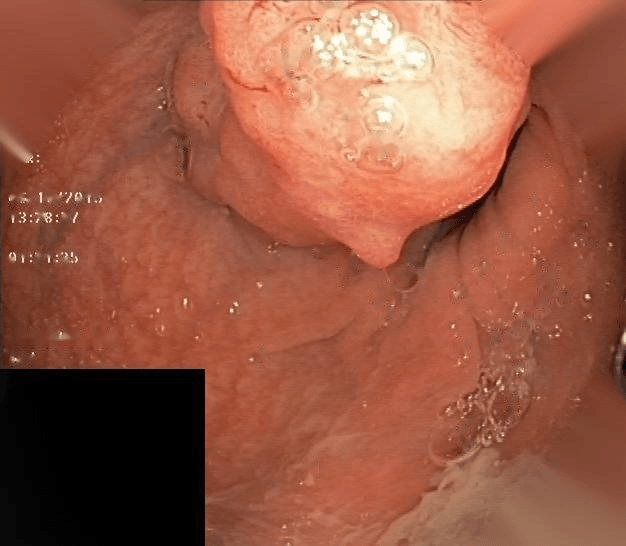

Refer to caption

(a) No abnormality

(b) Polyp

(c) Oesophagitis

(d) Ulcerative Colitis

Figure 1: Illustrations of question-answer pairs along with common abnormalities in gastrointestinal image from ImageCLEFmed-MEDVQA-GI-2023 dataset

The new dataset released for the ImageCLEFmed-MEDVQA-GI-2023 challenge is based on the HyperKvasir dataset [29], the largest gastrointestinal collections with more than 100,000 images, with the additional question-and-answer ground truth developed by medical collaborators. The development set and test set include a total of 3949 images from different procedures such as gastroscopy and colonoscopy, spanning the entire gastrointestinal tract, from mouth to anus. Each image has a total of 18 questions about abnormalities, surgical instruments, normal findings and other artefacts, with multiple answers possible for each, as shown in Table 1. Not all questions will be relevant to the provided image, and the VQA system should be able to handle cases where there is no correct answer. Figure 1 depicts several examples of question-answer pairs on common abnormalities in gastrointestinal tract, such as Colon Polyps, Oesophagitis, and Ulcerative Colitis. As shown in Figure 1(d), there are three possible answers to the question "What color is the abnormality?": "Pink," "Red," and "White", and a typical VQA system should be able to identify all three colors. In general, the image may contains a variety of noise and components that locates across abnormalities, such as highlight spots or instruments, which pose a significant challenge in developing efficient VQA systems for gastrointestinal domain.